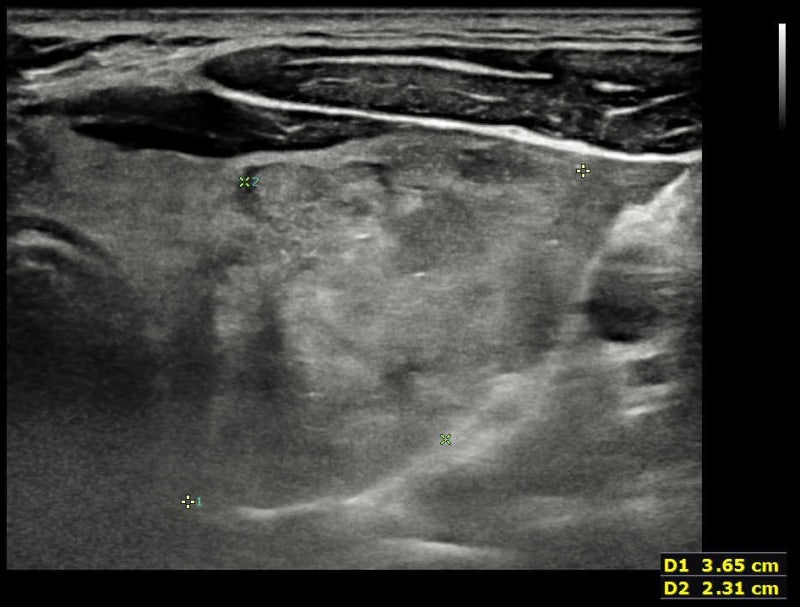

갑상선에 결절이 발견되면 옆 경부 림프절까지 잘 관찰해야 암 진단에도 도움이 되고 수술 범위를 정하는 데도 도움이 됩니다. 그런데 일반적으로 갑상선 암의 진단 환자도 옆 경부 림프절 검사를 게을리하는 일이 많습니다. 다른 병원에서 검사한 뒤 생큐 서울 이비인후과를 찾은 환자(712명)의 초음파 사진을 다시 검토한 결과 66%의 환자의 초음파 검사 사진에서 측 경부 검사가 빠지고 있었습니다.대학 병원 가운데 빅 5도 22%에서 탈락하며 빅 5를 제외한 대학 병원은 48%에서 탈락했어요.샌 환자들을 고마워서울 이비인후과에서 초음파 검사를 했는데, 약 6%의 환자에게서 측 경부 림프절 전이가 발견되었습니다.(해당 내용은 최근 대한 갑상샘 학회에서 발표했습니다.)관련의 증례를 하나 소개합니다.30세 남자 환자가 2년 전으로 건드리는 갑상선 결절에 대해서 상담하기 위해서, 생큐 서울 이비인후과- 내분비 내과 이·운정 원장 외래를 방문했습니다.2017-01-20대학 병원에서 초음파 검사와 총 생검을 실시했습니다만 옆 경부 림프절에 대해서는 전혀 검사를 벌이고 있지 않습니다. 당시 총 생검 결과는 양성 혹(benign follicular nodule이었습니다.*여기서 총 생검이 가는 바늘 흡입 세포 검사보다 항상 좋은 검사가 아님을 알 수 있습니다. (중략)2019-08-03시행한 고마워서울 이비인후과 초음파 사진은 다음과 같습니다.

좌갑상선결절